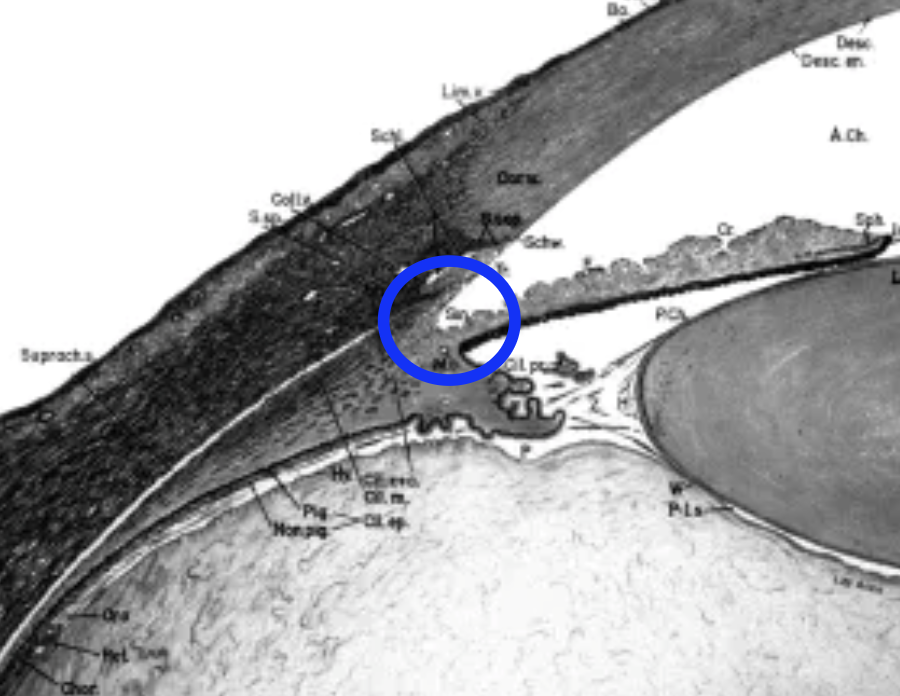

What is the “angle of the eye”?

“Iridocorneal angle”

location where the iris, ciliary body, cornea & sclera meet

What’s found in the “angle of the eye”?

Root of the iris

Ciliary body and band

Scleral spur

Schlemm’s Canal

Schwalbe’s line

TM

Where do the TM & Schlemm canal reside?

within the internal scleral sulcus

What is the Scleral spur?

a “lip” of sclera that projects into the base of the TM